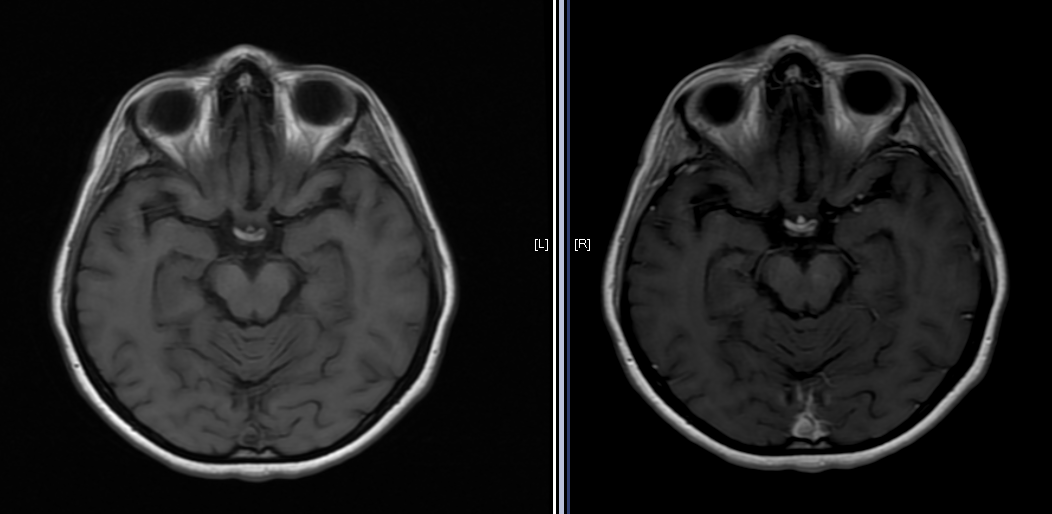

Objetivo: Relatar o caso de recidiva de herpes-zoster (HZ) em paciente com esclerose múltipla (EM) em uso de tratamento imunomodulador (natalizumabe) com evolução favorável. Descrição de caso: Mulher de 39 anos com diagnóstico de EM há 1 ano e 6 meses, previamente tratada com interferon 1a, começou tratamento com natalizumabe, desenvolvendo HZ após três meses de tratamento. HZ foi tratado com aciclovir, por sete dias, via oral. Seguimento ambulatorial após três meses de tratamento mostrou resolução completa das lesões, sem desencadeamento de neuralgia pós-herpética. Conclusões: As novas terapias para a EM podem estar relacionadas a diferentes tipos de efeitos adversos. Nem todos os casos de HZ, associados com novas terapias para EM, evoluem de forma desfavorável. Estudos são necessários para reconhecer os fatores de riscos para as formas graves de HZ em tais pacientes.